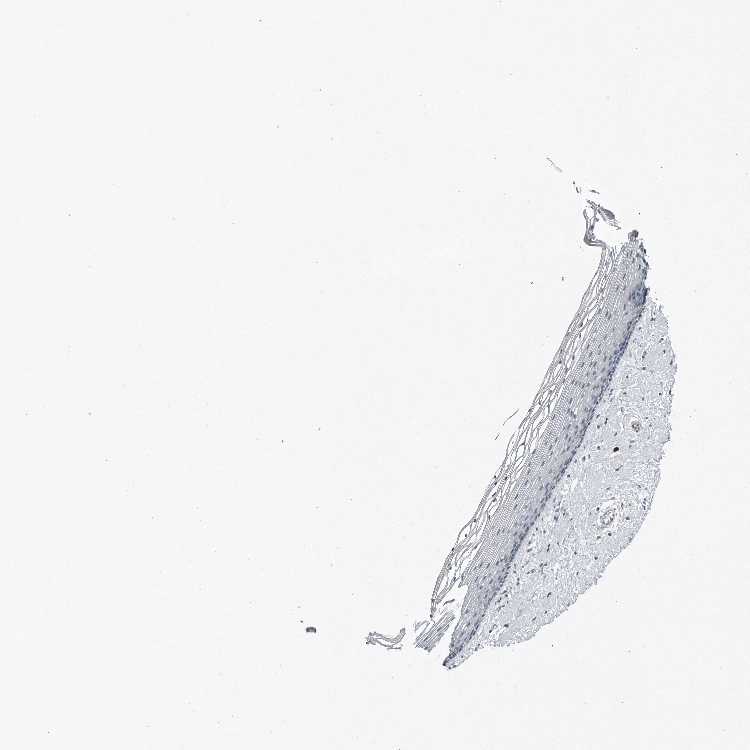

VAGINA - Antibody stainingi

Antibody staining in the annotated cell types in the current human tissue is reported as not detected, low, medium, or high, based on conventional immunohistochemistry profiling in selected tissues. This score is based on the combination of the staining intensity and fraction of stained cells.

Each image is clickable and will lead to virtual microscopy that enables deeper exploration of all samples and also displays staining intensity scores, fraction scores and subcellular localization as well as patient and tissue information for each sample.

Antibody CAB025802

Squamous epithelial cells Not detected